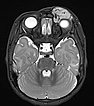

T2-weighted axial MRI with fat saturation. The mass medial to the left eye is relatively homogeneously hyperintense and sharply demarcated from the surrounding tissue. As a sign of strong arterial perfusion, some black, signal-free arterial vessels are seen in the lesion (“flow voids”). This is also typical of an infantile hemangioma.

T2-weighted axial MRI without fat saturation. The mass medial to the left eye is also relatively homogeneously hyperintense in this sequence and shows central flow voids. However, due to the lack of fat saturation, the mass is not as well demarcated from the surrounding adipose tissue.